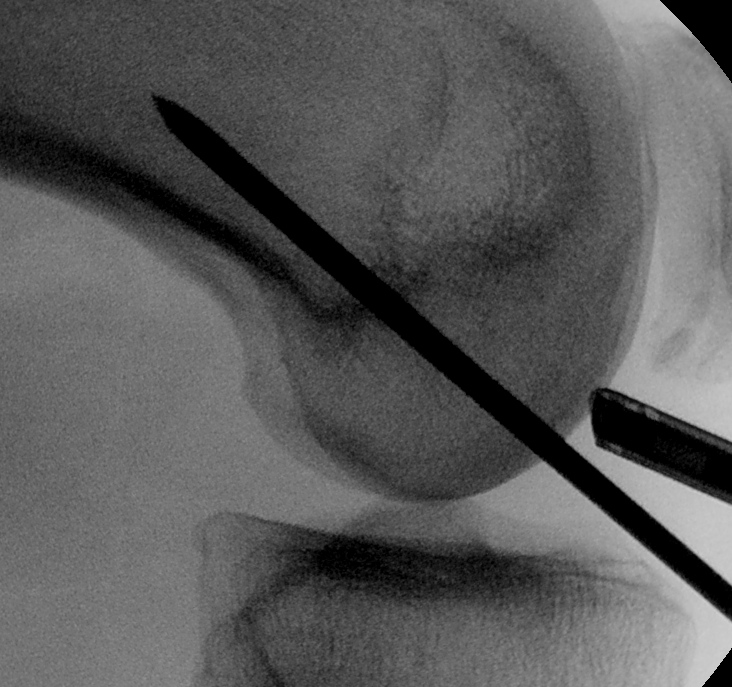

- II with perfect lateral of knee

- superimposed femoral condyles

Femoral entry point

- place beath pin just medial to patella tendon

- insert into femoral insertion of ACL on LFC

- check entry on lateral

- imagine posterior femoral condyle as circle

- entry point in centre, but 60% of distance posterior

- can also look inside knee with scope to confirm insertion

- drive out lateral femur as standard

- pull pin back through femur so that guide wire passes up into femur

- distal pin now in joint